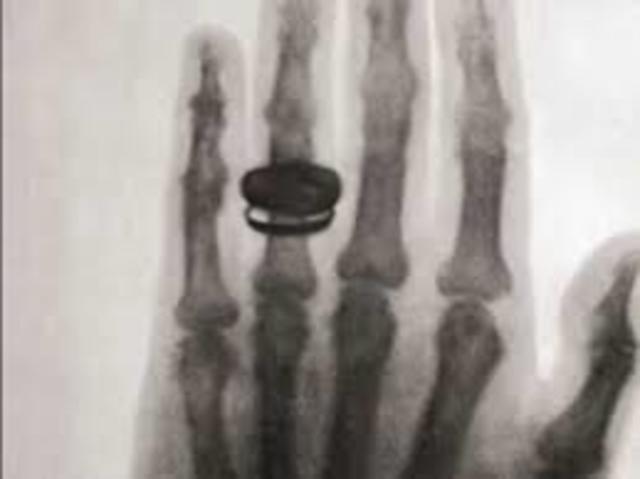

• x-ray machine

x-ray machine

German physicist Wilhelm Röntgen accidentally discovered X-rays. Within a year, the first radiology department opened in a Glasgow hospital, and the department head produced the first pictures of a kidney stone and a penny lodged in a child’s throat.